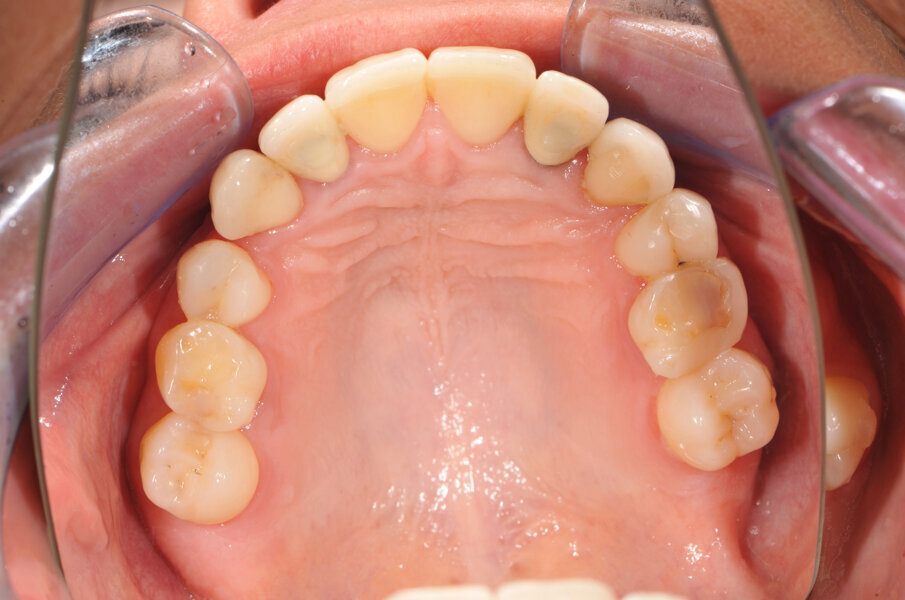

In deze casus is indertijd voor tissue level-implantaten gekozen en na ongeveer achttien jaar in functie is de esthetiek, mede door de vorm van de cuspidaten en het zichtbaar worden van de implantaten, discutabel te noemen (afbeelding 1 en 2).